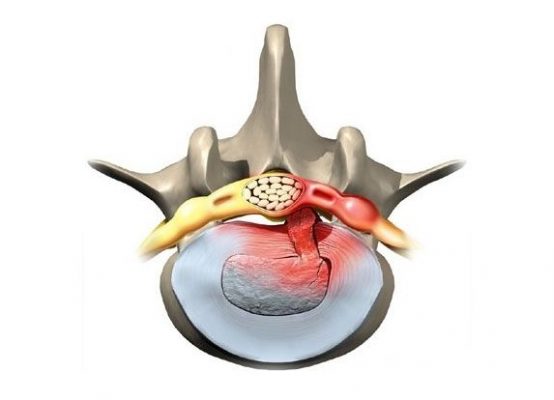

Одним из самых распространенных заболеваний поясничного отдела считается межпозвоночная грыжа. Грыжей межпозвоночного...

Межпозвоночная грыжа является заболеванием позвоночника, при котором деформированный позвоночный диск смещается, выходя...